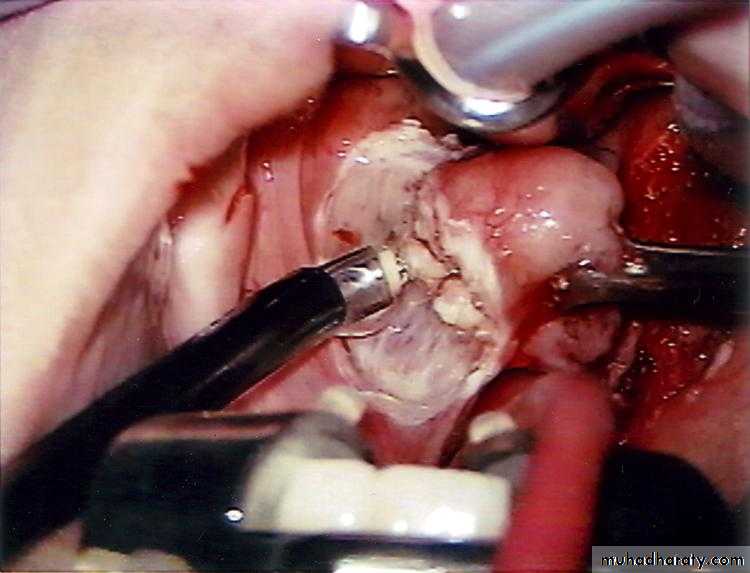

Treatment

I. Medical : Effective in early peritonsillar cellulitis.II. Surgical : when considerable swelling is present or in case of failure to medical treatment.

1. Incision of the abscess: this is undertaken at the point of maximum swelling of the soft palate. The classical site is at a point where an imaginary line through the base of the uvula is intersected by a perpendicular line from the junction of the anterior tonsillar pillar with the tongue.

The tonsils might be removed 6-8 weeks following quinsy.

2. Abscess tonsillectomy